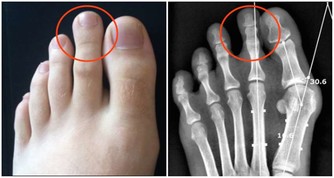

4、打好前列腺”保衛戰“。

美國國家癌症研究院的一項研究表明,

每天大蒜或蔥的攝入量超過10克的人,比攝入量少於2克的人患前列腺風險降低50%。